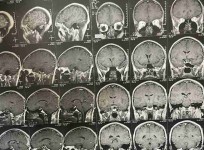

جراحات المخ